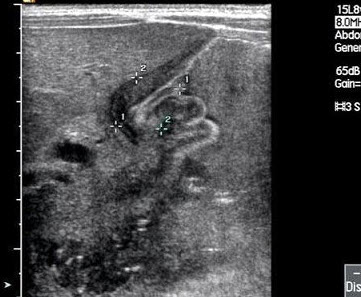

患者女47岁,皮肤、巩膜黄染,进行性加重2个月余,腹痛、腹胀,既往有胆结石病史。B超检查如图所示,根据超声声像图,诊断为()

A.胆总管癌并结石

B.胆总管胆泥淤积

C.胆总管结石

D.胆总管蛔虫

E.胆总管癌